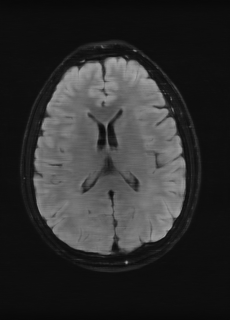

As we observe from the right image in Fig. 2, our BRM, both from MIMO and SISO settings, predicts the performance of dedicated models with a high correlation. We further choose the best three , and perform the last stage of fine-tuning accordingly to (6). A visual evaluation on real data is shown in Fig. 3. For simulated data, please refer to the Supplemental Material section.

Base on the best performing , we perceive that among , , and FLAIR, the results are best when is sampled the most. We suggest that this makes intuitive sense as images provide the best contrast out of the three sequences, which can compensate for the details lost in other images. The same observation can be made on the simulated data, where both and FLAIR show good contrast. When the time setting is changed to non-uniformity, we can see that our search for the best sampling strategy reflects the change. is sampled more as a result of faster acquisition time, while is still sufficiently sampled.

| Sequence | LR | SISO | MIMO | MIMO tuned | GT |

|---|---|---|---|---|---|

(a) 34.38/0.9371

(a) 34.38/0.9371

|

(b) 42.42/0.9883

(b) 42.42/0.9883

|

(c) 44.60/0.9920

(c) 44.60/0.9920

|

(d) 45.50/0.9940

(d) 45.50/0.9940

|

(e) PSNR/SSIM

(e) PSNR/SSIM

|

|

(f) 29.74/0.8903

(f) 29.74/0.8903

|

(g) 36.25/0.9734

(g) 36.25/0.9734

|

(h) 36.42/0.9752

(h) 36.42/0.9752

|

(i) 37.70/0.9832

(i) 37.70/0.9832

|

(j) PSNR/SSIM

(j) PSNR/SSIM

|

|

(k) 39.89/0.9311

(k) 39.89/0.9311

|

(l) 43.94/0.9864

(l) 43.94/0.9864

|

(m) 44.74/0.9883

(m) 44.74/0.9883

|

(n) 45.49/0.9894

(n) 45.49/0.9894

|

(o) PSNR/SSIM

(o) PSNR/SSIM

|